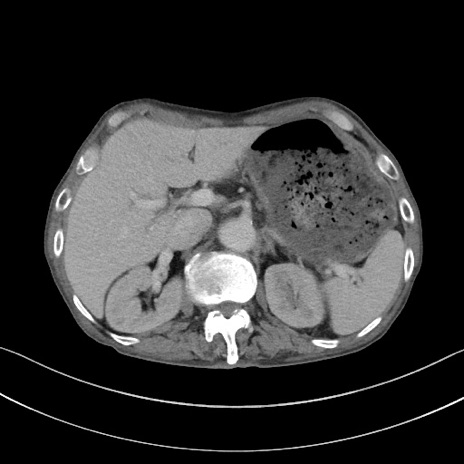

症例3(横断像)

【症例】 70歳代男性

【主訴】右鼠径部腫瘤、疼痛

【現病歴】本日朝より上記主訴あり、受診。

【既往歴】膀胱癌にて膀胱全摘、両側尿管皮膚瘻

【データ】WBC 5600、CRP 0.56